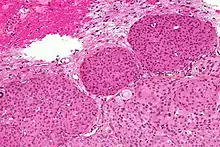

Se requiere de una radiografía simple de cráneo, en la que se podrán observar con relativa frecuencia surcos vasculares aumentados de tamaño, signos de calcificación o hiperostosis o signos de hipertensión intracraneal crónica. En una TAC suelen aparecer lesiones muy bien delimitadas y usualmente se muestra una lesión hiperdensa tras administración de contraste que puede estar rodeado de edema y de base de implantación amplia. Es la modalidad que muestra de mejor manera las calcificaciones tumorales. Estas pueden ser nodulares, puntiformes o densas. La TC es muy efectiva para demostrar la hiperostosis (15-20%), osteolisis y erosión en el sitio de la inserción dural. También muestra el ensanchamiento de los surcos vasculares de la calota (arteria meníngea media). Se precisará en aquellos casos donde se necesite un mayor detalle óseo.